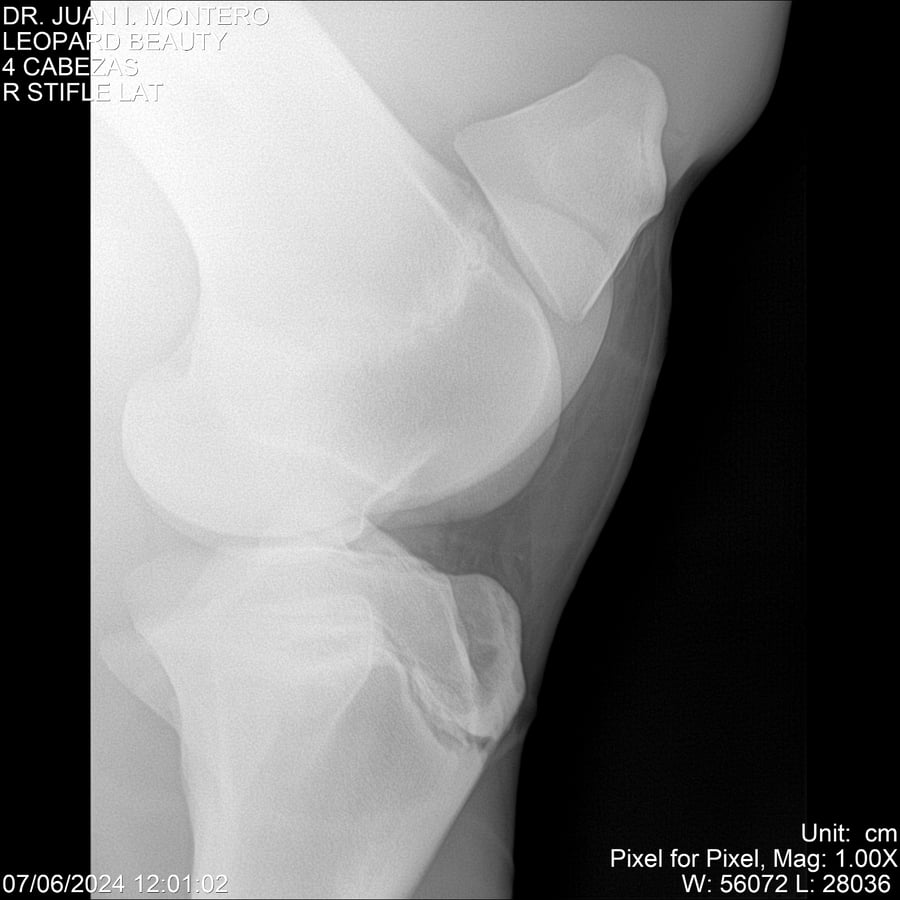

LOTE 16, LEOPARD BEAUTY Lote Anterior Volver al remate Lote Siguiente Ficha Contacto Montevideo - Ficha del Lote Identificador: #281095 Categoría: Yeguarizos Montevideo - 50 Visualizaciones ClicData Contacto Empresa: Abelenda N. R., Walter Hugo Nombre*: Teléfono* : E-mail* : Mensaje Enviar Registrese gratis Este contenido Exclusivo está disponible sólo para usuarios registrados Ingresar